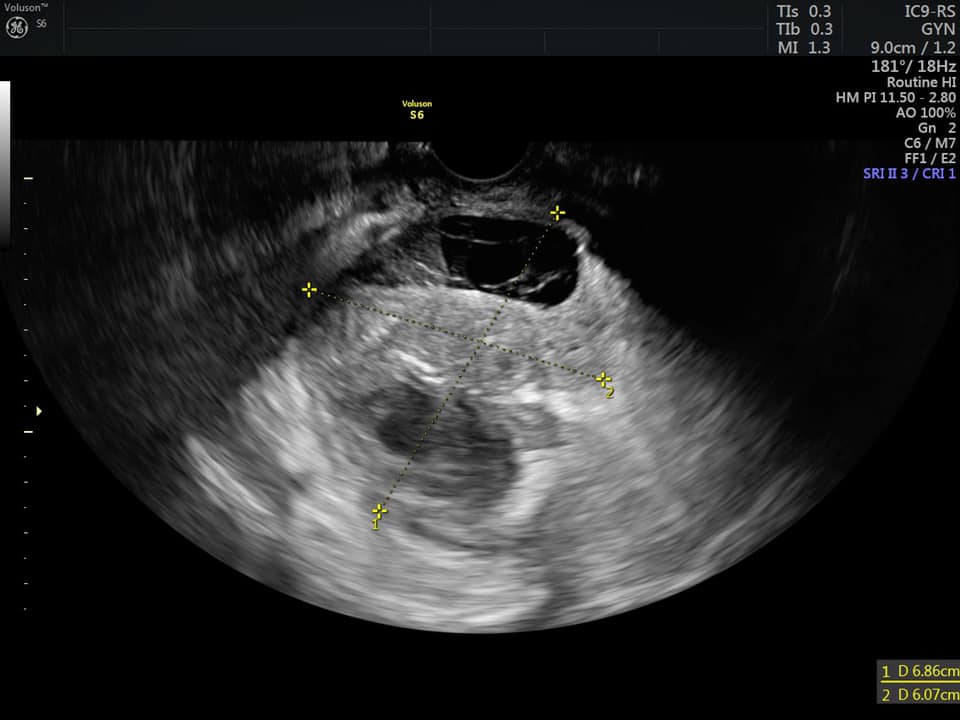

КТ диагностика тубоовариального абсцесса: Подходы и изображения

Раздел: Объективный взгляд